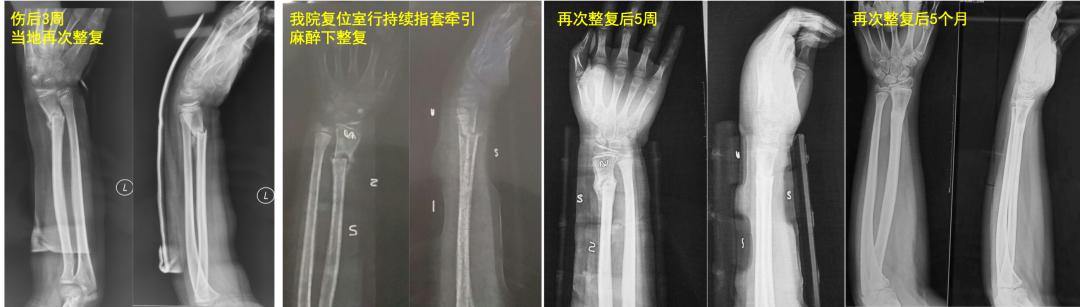

老师: 下面两个病例,分别是9岁4个月男孩的前臂中段骨折,保守治疗后3个月骨折对位、愈合良好。另外一个12岁男孩,早期外院保守治疗,三周时骨折再移位,于我院再次整复后恢复满意。

学生:儿童前臂骨折中,哪些是不稳定、保守治疗效果不好的? 老师: P. Schmittenbecher等回顾分析了1143例儿童前臂骨折,97.8%接受保守治疗,随访3-13.5年。结果中或差的比例为13.9与6.9%,有57%需接受二次骨折整复。提出骨折保守治疗疗效不佳与骨折类型密切相关:前臂近1/3骨折、同平面双骨折以及骨折线斜行合并背向成角。对这些儿童前臂骨折,治疗选择时需要警惕。

学生:会出啥问题啊? 老师: 对于11岁的孩子来说,切开复位钢板固定,损伤太大,对骨折端愈合微环境影响很大。如果术后管理不当的话,会大大增加骨折不愈合的风险。就像下面例子中的5岁孩子,前后经历了5次手术,反而问题越来越严重……